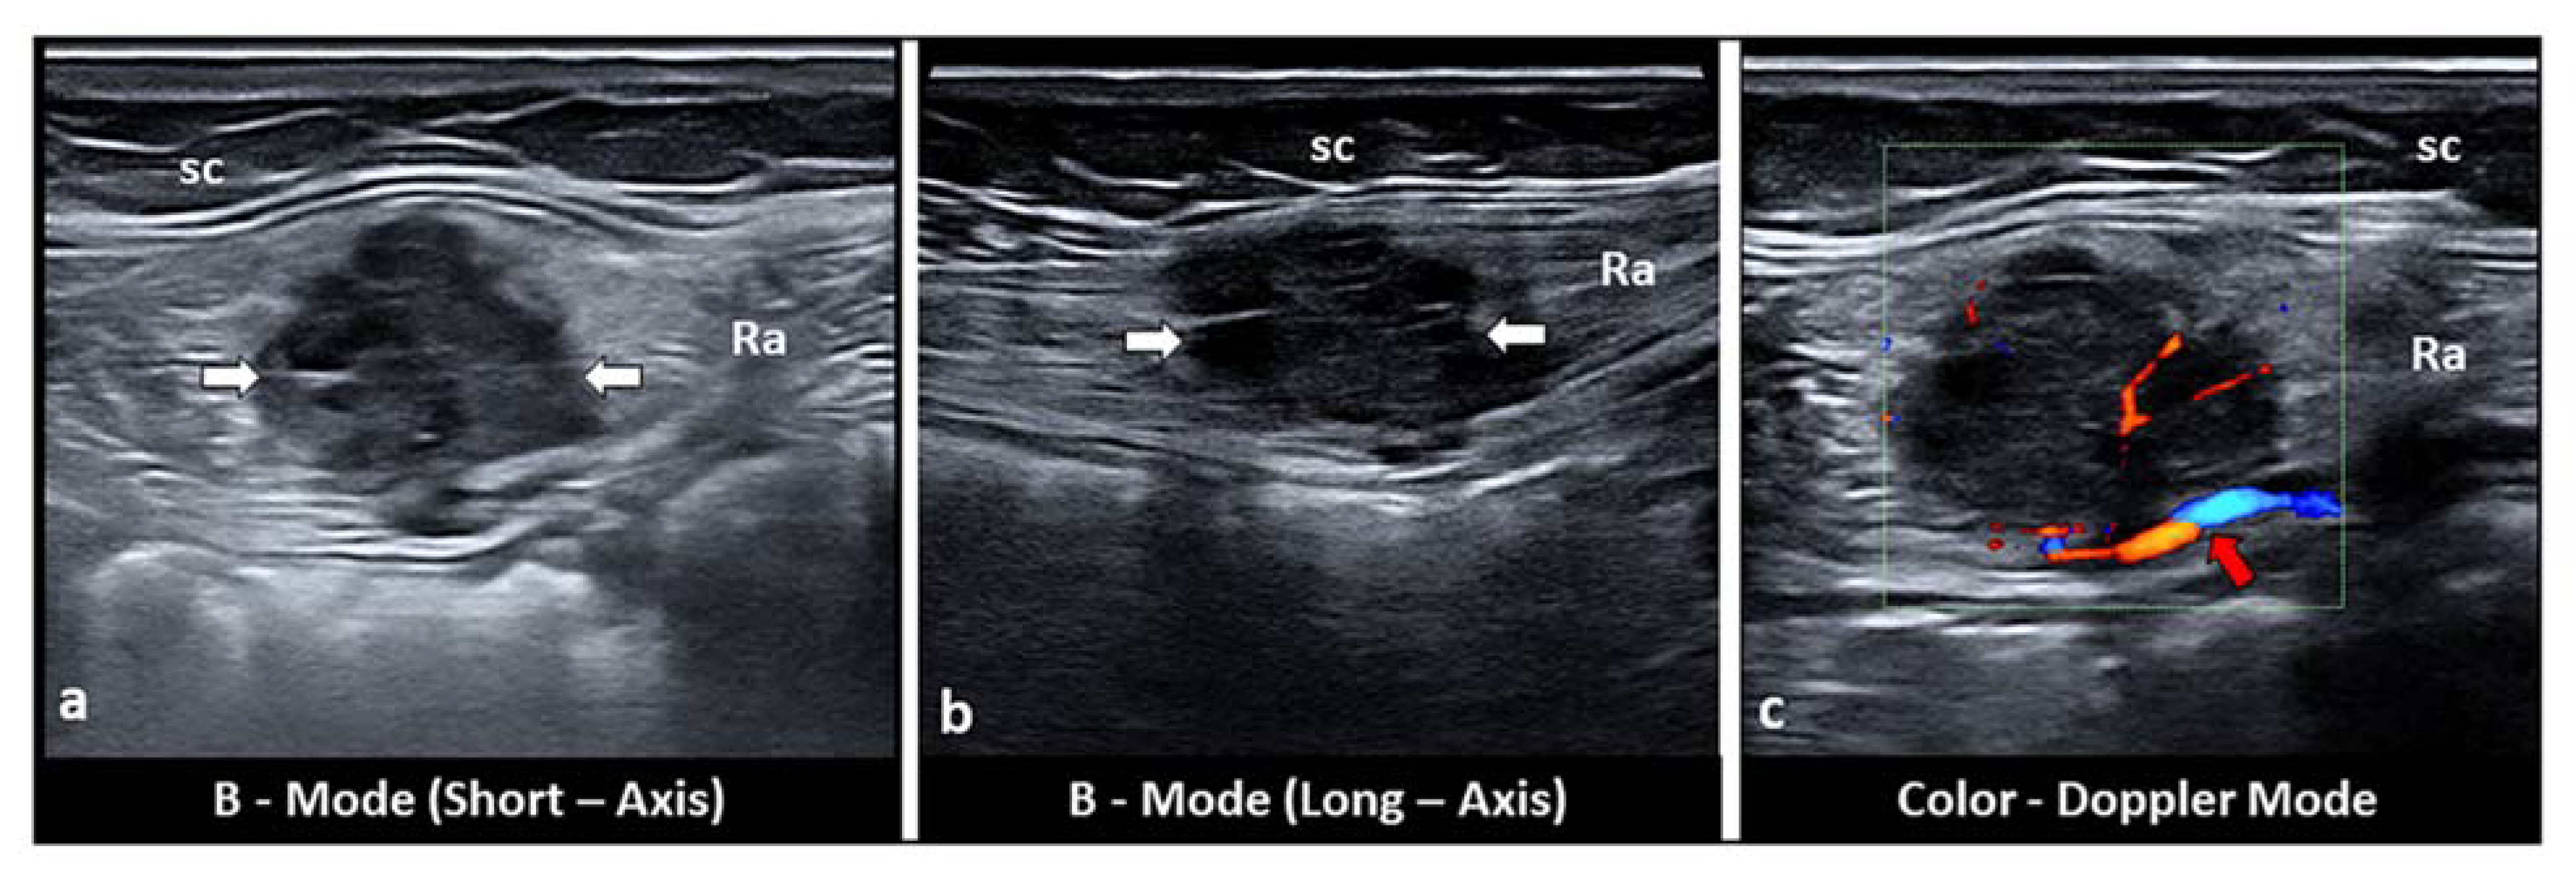

5. Intramuscular Endometriosis